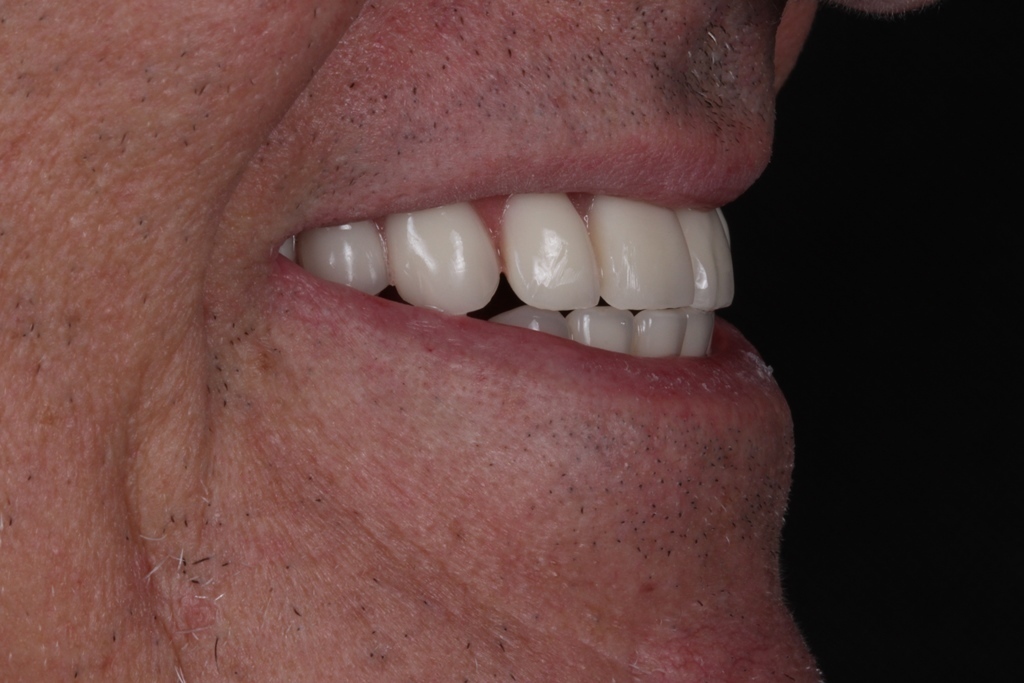

PRÓTESE TOTAL FIXA EM IMPLANTES

J.L.E.B.